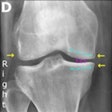

Trattnig shows how MRI depicts osteoarthritis, bone marrow edema